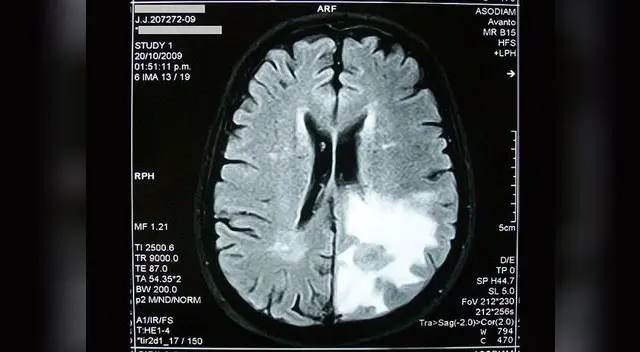

Yair Clavijo, futbolista de la reserva del Sporting Cristal, falleció debido a un edema cerebral con herniación de amigdalas cerebelosas y una miocardiopatia hipertrofica, de acuerdo a los resultados arrojados por el certificado de la necropsia de ley, según informaron medios locales.El documento realizado por los médicos legistas María Luisa Valencia Tejada y Evelyn Casamanca Monteagudo, también indica que el agente causante sería una patología cardíaca. El cuerpo de Yair ingresó ayer por la tarde a la Morgue Central del Cusco, trasladado desde el hospital de Urcos donde se certificó su deceso.Es preciso indicar que en estos momentos, el cadáver de Clavijo viene pasando por el proceso de embalsamamiento respectivo, en una funeraria de la Ciudad Imperial, para facilitar su trasladado a Lima en las próximas horas. Familiares del joven futbolista se hicieron presentes en la morgue para retirar del cadáver de Yair, y evitaron dar alguna declaración a la prensa.SOBRE EL EDEMA CEREBRALEdema cerebral es la acumulación de líquido en los espacios intra o extracelulares del cerebro, donde las neuronas cerebrales aumentan su tamaño debido a un aumento anormal del volumen de plasma intracraneal.Las principales causas son la hiponatremia, isquemia, accidente cerebrovascular y traumatismos craneoencefálicos (rotura de los vasos sanguíneos que provoca una hemorragia cerebral, aumentando el cuerpo celular de las neuronas mediante ósmosis).El Edema Cerebral también puede estar provocado por hipoxia de altitud, siendo denominado como "Edema Cerebral de Altitud". El distrito de Urcos se ubica a 3.158 msnm.SOBRE LA MIOCARDIOPATÍA HIPERTRÓFICALa miocardiopatía o cardiomiopatía hipertrófica es una enfermedad del miocardio (músculo del corazón), donde una porción de él está hipertrofiado o engrosado sin causa aparente.La importancia principal de la miocardiopatía hipertrófica radica en ser una de las causas de muerte súbita cardíaca en cualquier grupo de edad y una causa importante de síntomas cardíacos debilitantes.